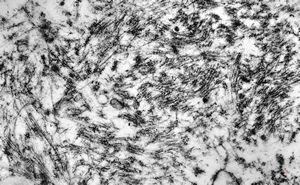

M,56y. | amyloidosis - tendon